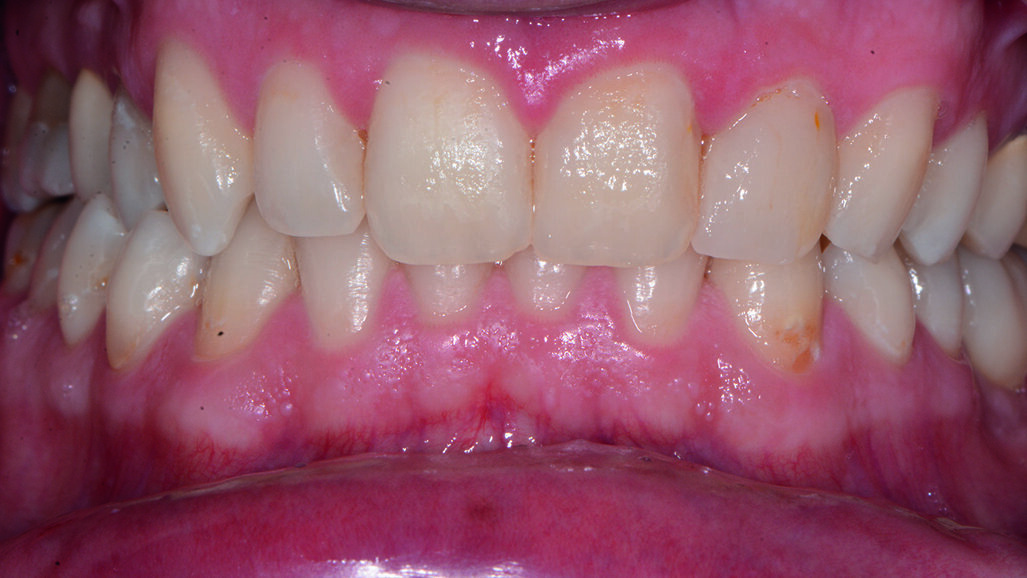

Si presenta alla nostra attenzione un paziente di sesso maschile, di anni 22, non fumatore, in apparente buona salute sistemica, per sottoporsi ad una seduta di igiene orale professionale e migliorare l’estetica del sorriso.

Durante l’esame obiettivo (Figg. 1a, 1b) rileviamo il danno iatrogeno da terapia ortodontica precedente alla visita e riscontriamo la presenza di processo carioso ICDAS 3 in zona 33 e in zona 47, white spots in zona 31 e 41. Durante l’esame obiettivo, l’ausilio della videocamera intraorale Sopro-Care (Acteon) permette, tramite filtri appositi, di evidenziare in modo rapido e accurato le zone di demineralizzazione e le aree infiammate e di mostrarle al paziente in real time, rendendolo attivamente partecipe e consapevole della situazione clinica (Figg. 2a-2f). I ricercatori del Baylor College of Dentistry hanno dimostrato che il 23,4% dei pazienti ha sviluppato almeno una white spot lesion durante il trattamento ortodontico.

Il paziente ha espresso la sua soddisfazione alla vista dell’efficace risultato del trattamento ed ha voluto fissare l’appuntamento successivo per il controllo e per le successive terapie conservative dei processi cariosi (Fig. 15). Al paziente è stata raccomandata una particolare attenzione al controllo di biofilm batterico domiciliare e per il controllo chimico è stato suggerito l’utilizzo del dentifricio Sensodyne Repair and Protect (GSK), che grazie alla tecnologia Novamin remineralizza riformando uno strato di idrossiapatite simile in corrispondenza delle lesioni smaltee e, sensodyne collutorio a base di sali di potassio e di fluoruro di sodio.